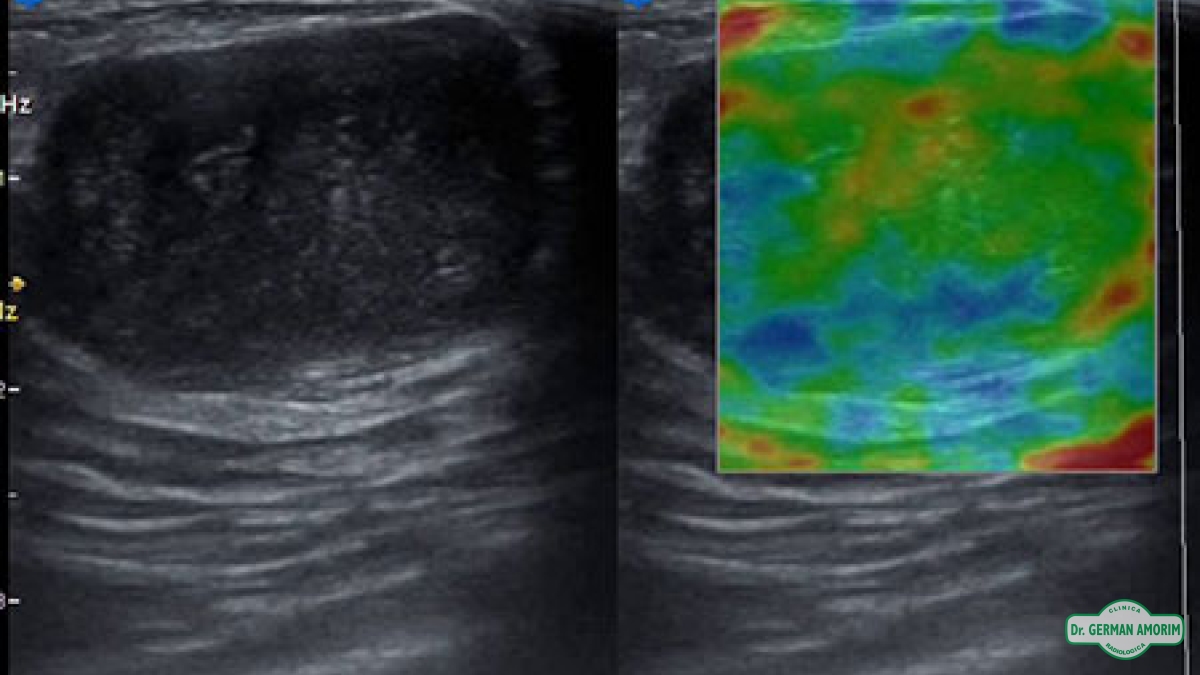

La elastografía es un método de diagnóstico complementario que utiliza los ultrasonidos para valorar la elasticidad o dureza de un segmento de un órgano o de un nódulo en estudio, mediante la tensión y compresibilidad que producen las ondas ultrasónicas en los tejidos del organismo en tiempo real.

Desde su invención, se han descrito múltiples aplicaciones en el estudio de los tejidos de la mama, próstata, tiroides y vasos sanguíneos.